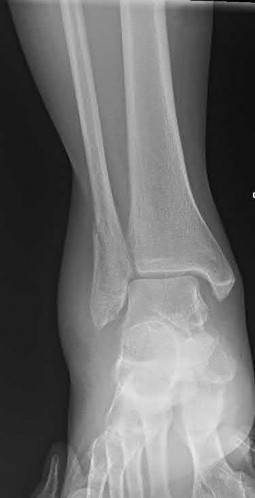

A 25-year-old male sustains an ankle fracture dislocation and undergoes open reduction and internal fixation. He returns to clinic five months following surgery complaining of continued ankle pain and instability with weight bearing. His immediate post-operative AP radiograph is seen in Figure A. Which of the following could have prevented this patient from developing persistent pain?

The patient presents with continued ankle pain and instability following open reduction and internal fixation. The radiograph in figure A demonstrates inadequate restoration of fibular length, likely leading to continued tibiotalar instability.